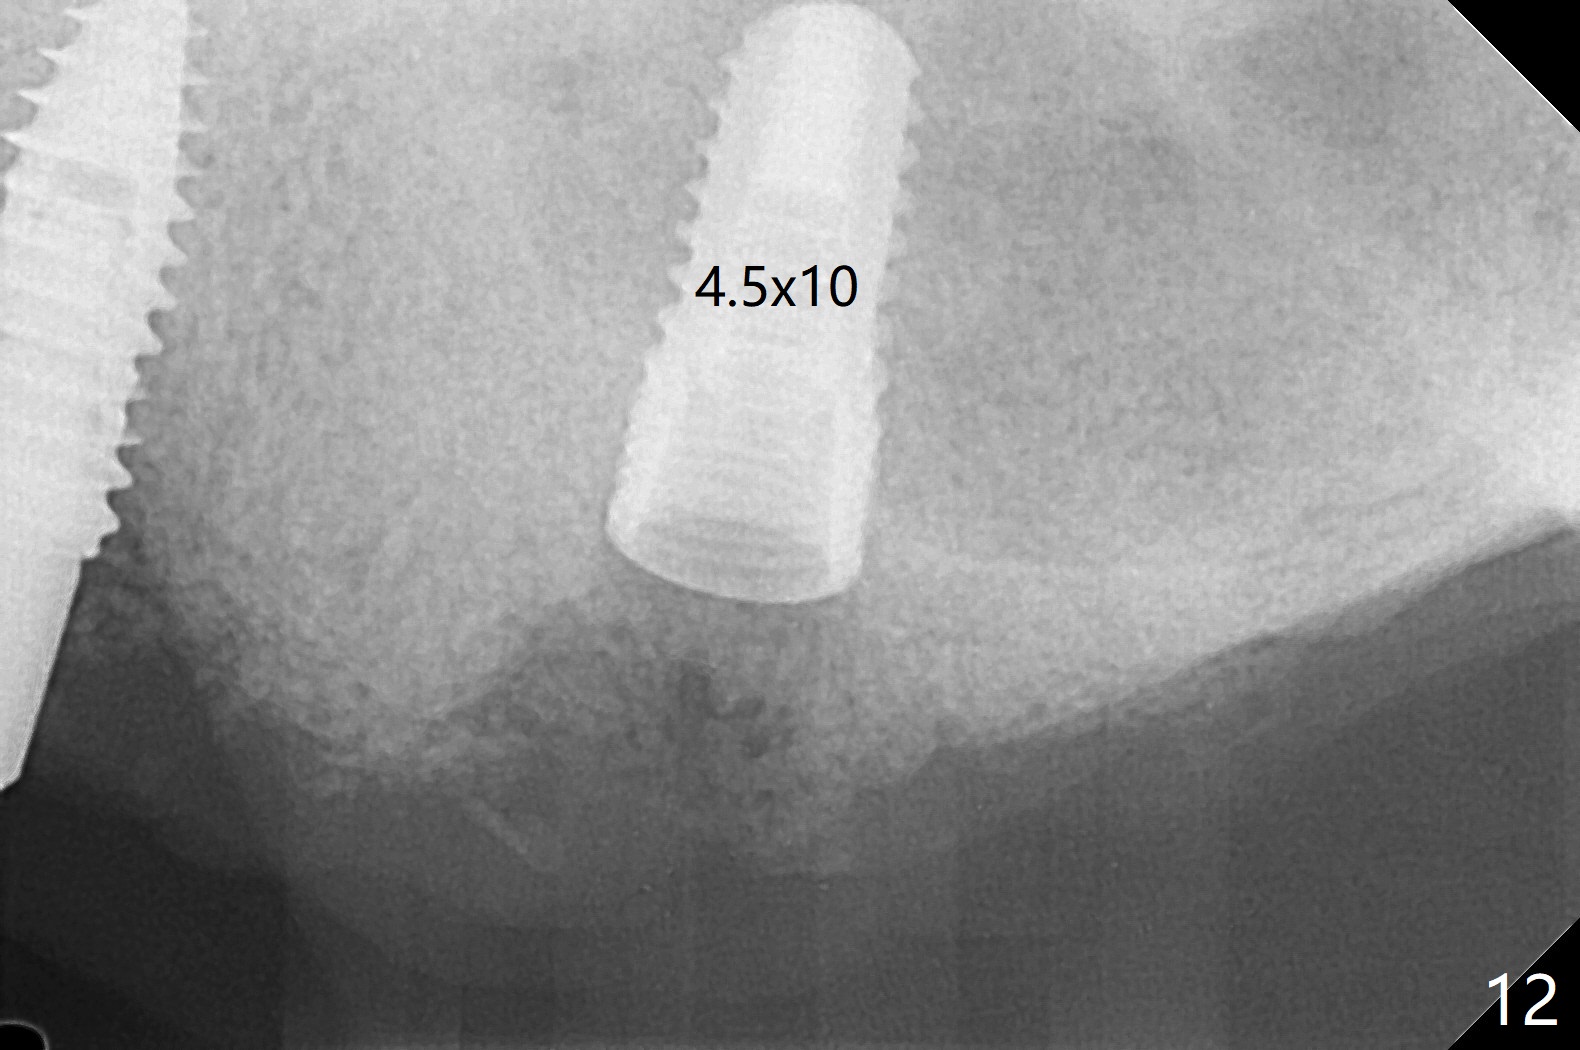

Osteotomy at #13 starts blindly (no incision or tissue punch) with bone expanders. After insertion of parallel pins, intraop CT shows that it is palatal with apparently buccal low bone density (Fig.1); the osteotomy for implant (Fig.2 green) should be shifted buccal and tilted mesial (red, parallel to #11) with incision. In contrast the position, trajectory and depth (Fig.3 <) of the initial osteotomy are acceptable at #11. The implant will be placed as it is (Fig.4). After taking a postop PA (Fig.5), the implant at #11 is placed a little deeper to make sure its slightly subcrestal placement (including distal incision at #11). Following placement of 3.5x4 and 3 mm ball abutments at #11 and 13, cortical allograft with PRF is placed around the implants, especially buccal (Fig.6,7 <). After suturing, the profile of the ball abutments is too low for RPD retention. Due to gravity other than bone density, the number of ball abutments for the maxilla should be more than for the mandible. Soft reline is done to the patient's satisfaction. The retention of the upper RPD after soft reline is satisfactory without pain 7 days postop (Fig.8). The implant at #13 is loose nearly 3 months postop (Fig.9 *: bone loss). The implant is removed while the ball abutment is untightened; the sinus floor is present. It appears that a longer and larger implant is necessary; a 4.5x10 mm dummy implant is unable to be seated deep or achieve primary stability (Fig.10). After sinus lift with 3 mm Bicon osteotome without bone graft, the dummy implant accomplishes the 2 tasks mentioned above (Fig.11). However there is no corresponding definitive implant in stock. Implant system needs to be changed; with a change in implant driver, the depth control is lost. The final implant is placed deep (Fig.12). With back up, stability is lessened; a healing screw is placed; with collagen plug, the wound is sutured (Fig.13). The wound heals 1 week postop (Fig.15). The RPD is soft relined. Retention from the ball abutment at #11 is apparently critical. The RPD and #11 implants (4 months postop) are stable, while the wound at #13 heals 1.5 months postop (Fig.15). There is space around the implant 5.5 months postop (Fig.16 *). The 5x10mm SM implant is found to be loose upon uncover and removed. After debridement, 5.3x8 mm SM and 5.5x9 mm IBS dummy implants are inserted without stability, while 6x9 mm definitive one with stability (Fig.17). Cortical allograft is placed in deficiency areas (*). The osteotomy has no roof (sinus floor), but the sinus membrane is intact. Small amount of bone graft (Fig.18 *) is placed before implantation. There appears to be bone around the new implant (Fig.19 (3D sagittal section) *).